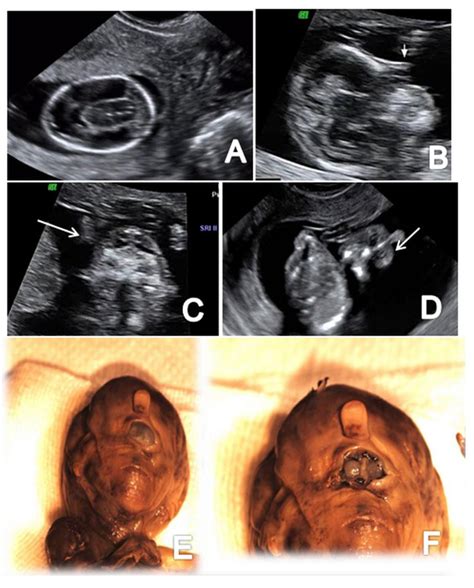

• Visualization of the Fetus: The sonographer will capture images of the fetus, including the head, abdomen, and limbs. These images help to assess the overall development and growth of the baby.

• Nuchal Translucency Measurement: The sonographer will measure the thickness of the fluid behind the baby's neck. This measurement, known as nuchal translucency, is used to screen for chromosomal abnormalities.

• Anatomy Check: The scan will also check for the presence of the nasal bone and other anatomical structures, which can provide additional information about the baby's health.

The 12 week pregnancy sonography can reveal a variety of findings, some of which may require further investigation. Here are some common findings and their implications:

• Increased Nuchal Translucency: A thicker than normal measurement may indicate an increased risk of chromosomal abnormalities or other genetic conditions.

• Absent Nasal Bone: The absence of the nasal bone can be associated with certain chromosomal abnormalities, such as Down syndrome.

• Structural Abnormalities: Any structural abnormalities, such as heart defects or neural tube defects, will be noted and may require further evaluation.